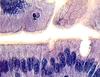

what is pictured

hyaline cartilage